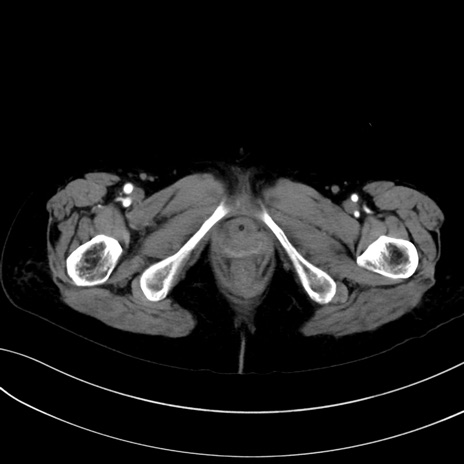

症例13 CT(横断像)1日半後